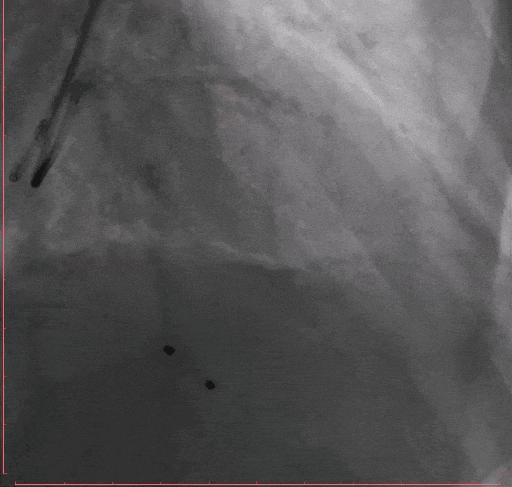

Step 6.主动脉瓣球囊预扩张

Step 7. Taurus 26 瓣膜释放至工作位造影确认位置

Step 8 Taurus 26 瓣膜释放后造影

Step 9. 患者出现心衰,血流动力学不稳,予以IABP植入

术后复查超声心动图:人工瓣膜功能正常,主动脉瓣峰值流速179m/s,平均压差7mmHg,未见瓣周漏。